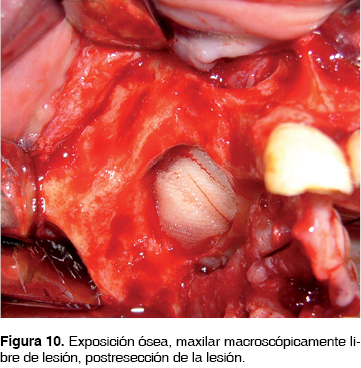

CASO 4

Masculino de 64 años de edad alérgico a la penicilina, con antecedentes de carcinoma prostático tratado mediante radioterapia prostática y cirugía 5 años antes, el cual inicia su padecimiento 2 meses previos a la consulta posterior a la extracción de segundo premolar y primer molar superior derecho, evolucionando inadecuadamente con dolor, halitosis, edema periférico facial, así como aumento de volumen en región maxilar posterior derecha. En la biometría hemática presentó hemoglobina de 11.3 g/dL, leucocitos de 4.44 cpm, glucosa de 84 g/dL. Se inicia tratamiento farmacológico con clindamicina 600 mg IV cada 8 hrs. Posteriormente se realiza hemimaxilectomía subtotal derecha bajo anestesia general inhalatoria balanceada, mediante abordaje cirunvestibular de 6 cm con disección de tejidos hasta exposición ósea, (Figura 9) observando áreas óseas de necrosis, se realiza resección ósea de 7 x 6.5 cm (Figura 10). Se verifican clínicamente bordes óseos libres de lesión y se sutura con ácido poliglicólico 3 ceros.

Se confirma osteomielitis crónica maxilar histopatológicamente con bordes libres de lesión, se inicia tratamiento ambulatorio con clindamicina 300 mg cada 8 h por 30 días. Actualmente con 2 años de evolución sin datos de recidiva.